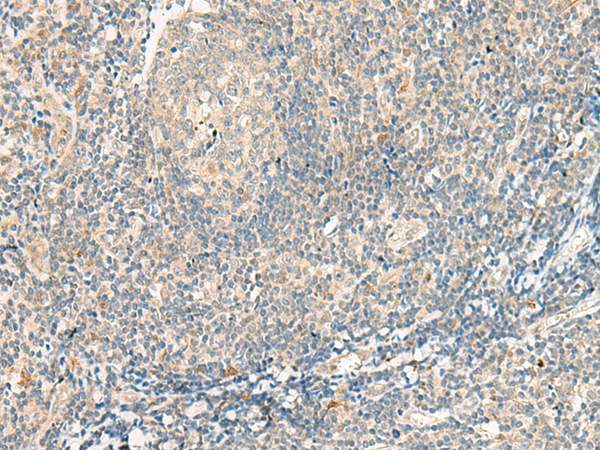

分类: 科研抗体货号: P13531别名: C3G; GRF2应用: IHC反应种属: Human